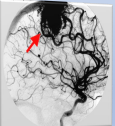

• Dr. José A. Rodríguez realizó la primera angioplastia coronaria, en paciente varón con un infarto del miocardio inferior

Dr. Domínguez y Dr Marcos Córdoba realizan una angioplastia a la arteria coronaria derecha, en paciente varón de 54 años con angina de pech0